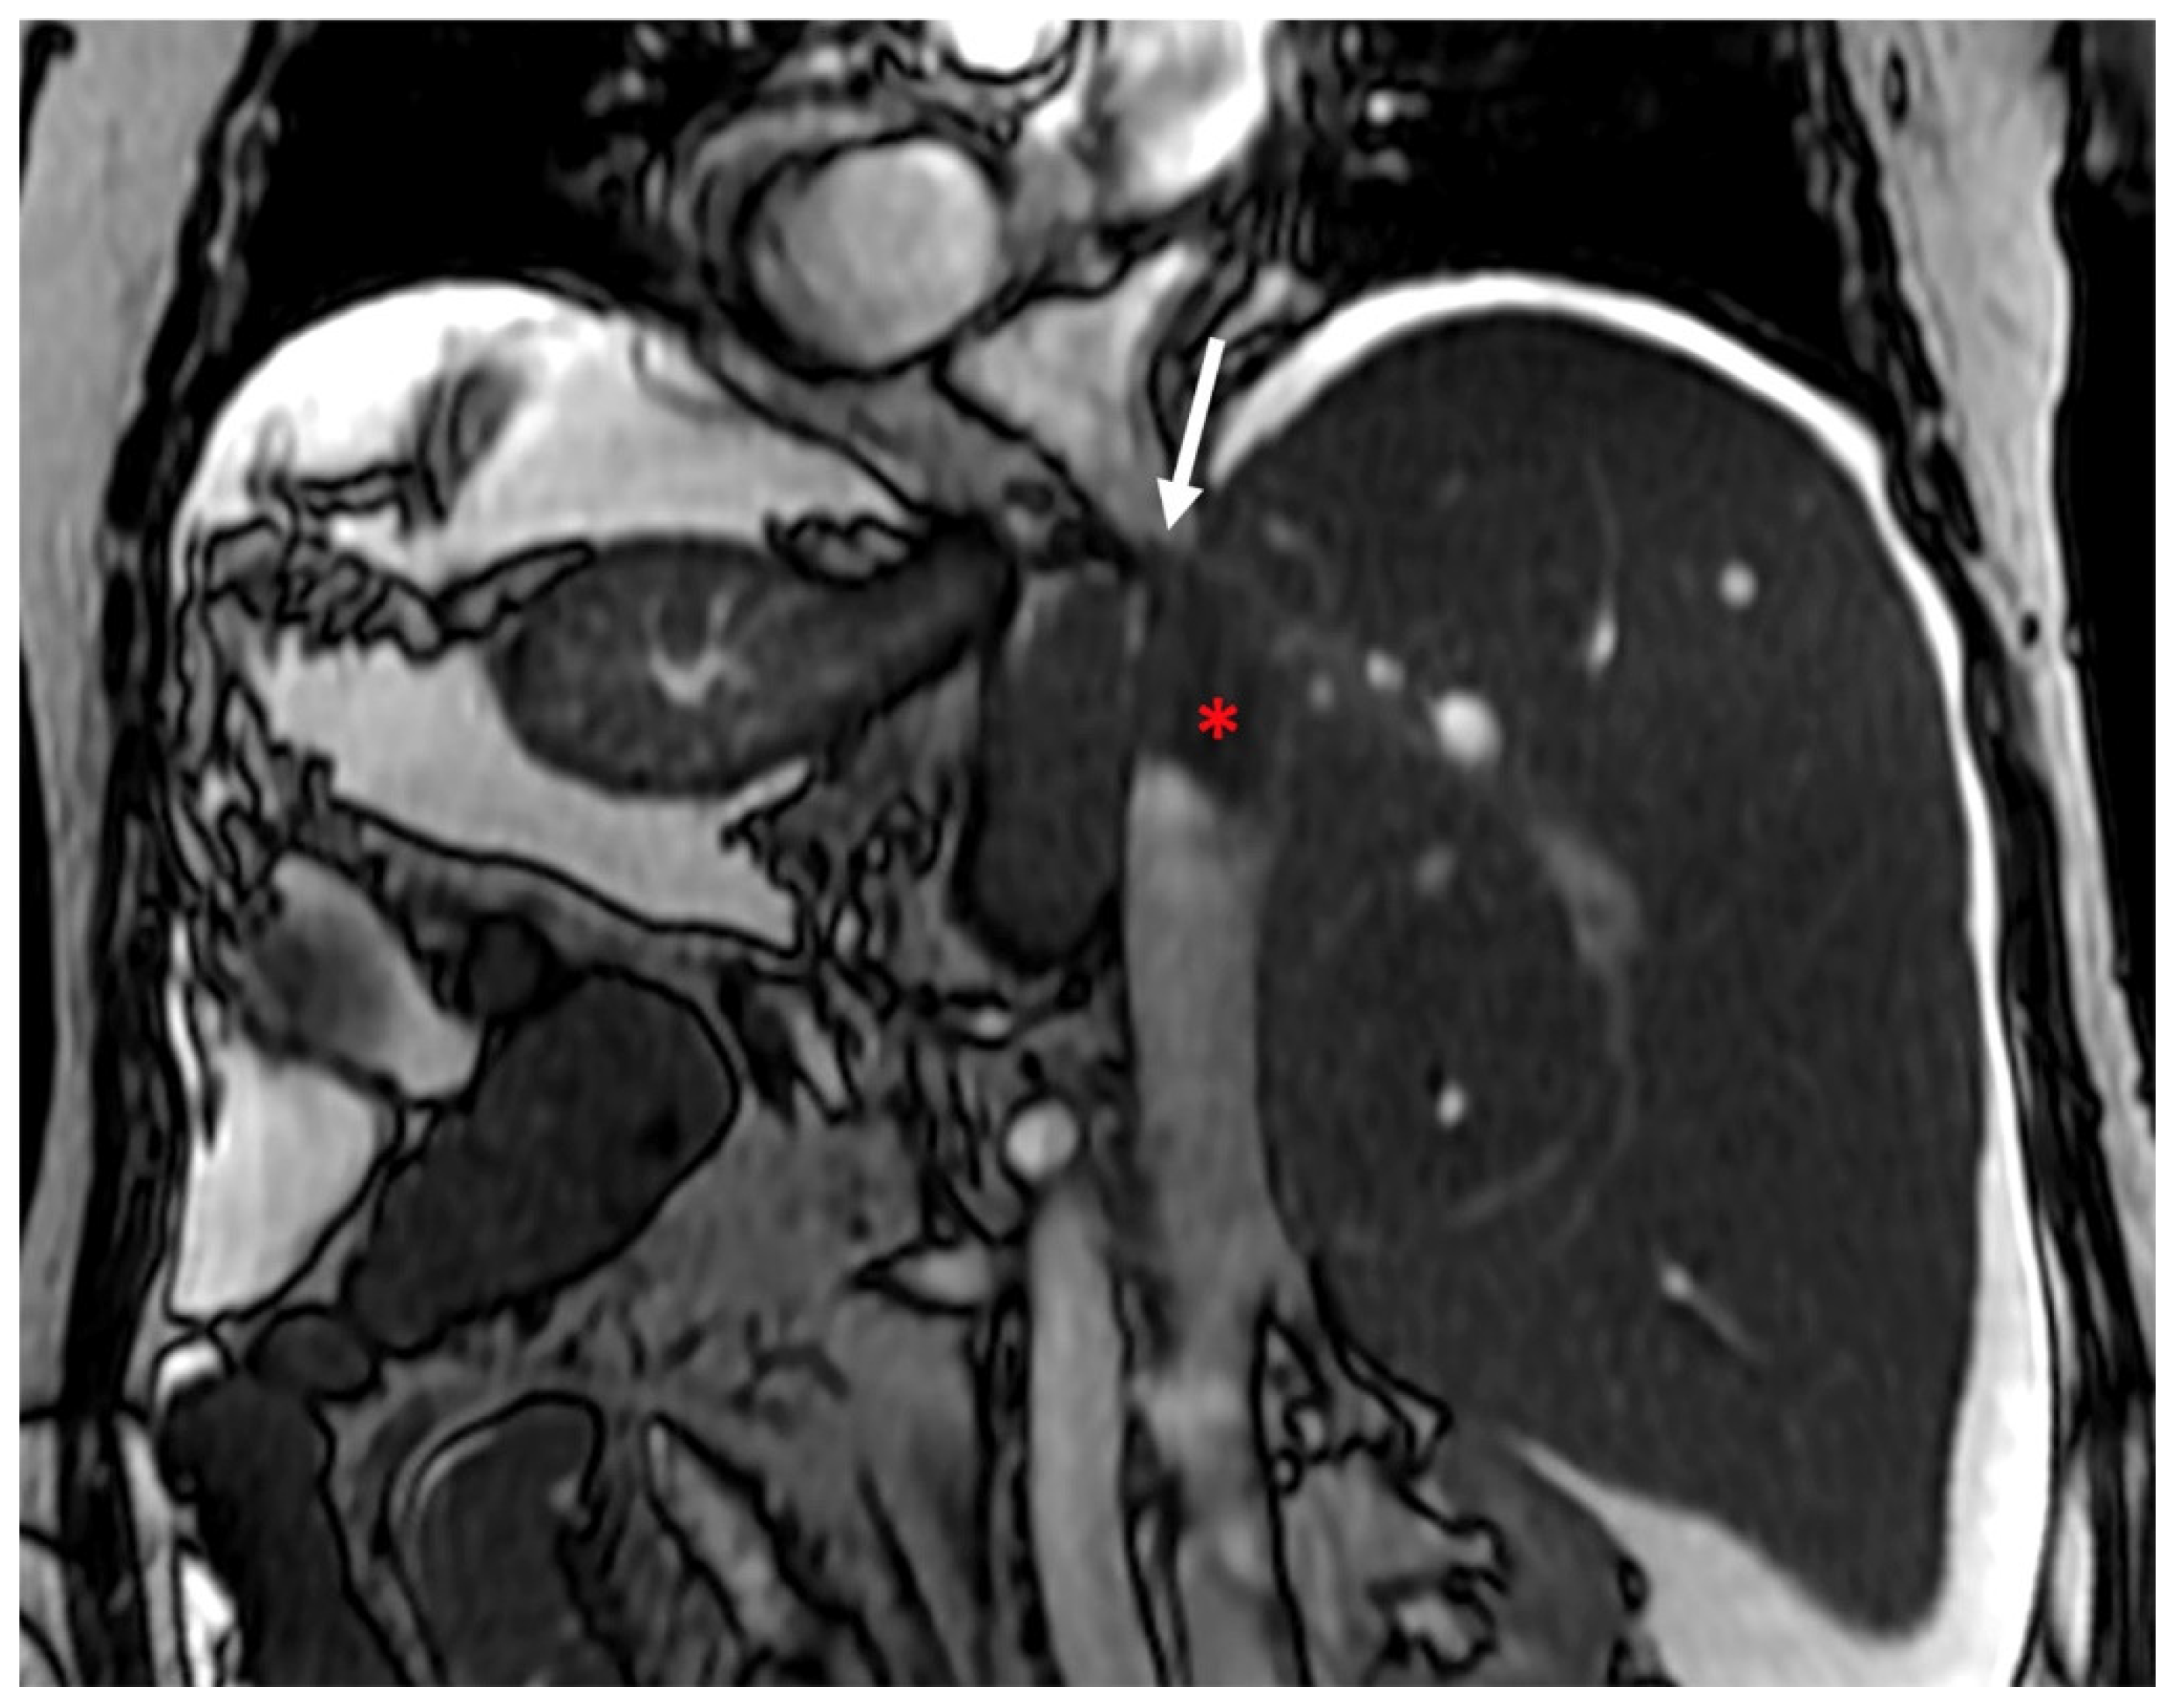

3.1. Ultrasounds: What to Look For

3.2. Computed Tomography and Magnetic Resonance: What to Look For

| CDUS | HV thrombosis ICV thrombosis and compression (better studied on CT/MRI) PV thrombosis HV demodulation Intra-hepatic collateral vessels Stagnant, reduced and/or hepatofugal PV flow Focal acceleration of velocity corresponding to stenosis Ascites Caudal lobe enlargement |

| CT | Liver morphology alteration Acute phase: “zonal” or “flip-flop” perfusion Chronic phase: “mosaic” perfusion Extra- and intra-hepatic collaterals Site and extension of thrombosis Pre-endovascular treatment assessment Hepatic artery and caudate vein enlargement Hepatic Nodules Ascites and caudal lobe enlargement |

| MRI | Characterization of nodules (FNH-like nodules vs. HCC) T1-w decreased signal in hypoperfused regions, corresponding to high T2-w SI T2*-w flow void corresponding to thrombus. Hypointensity along the occluded vessels |